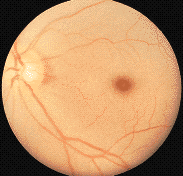

(写真左:網膜中心動脈閉塞症、写真右:網膜動脈分枝閉塞症

ともに発症から時間が経過した写真)

(出典:「目と健康シリーズ 6」 三和化学)